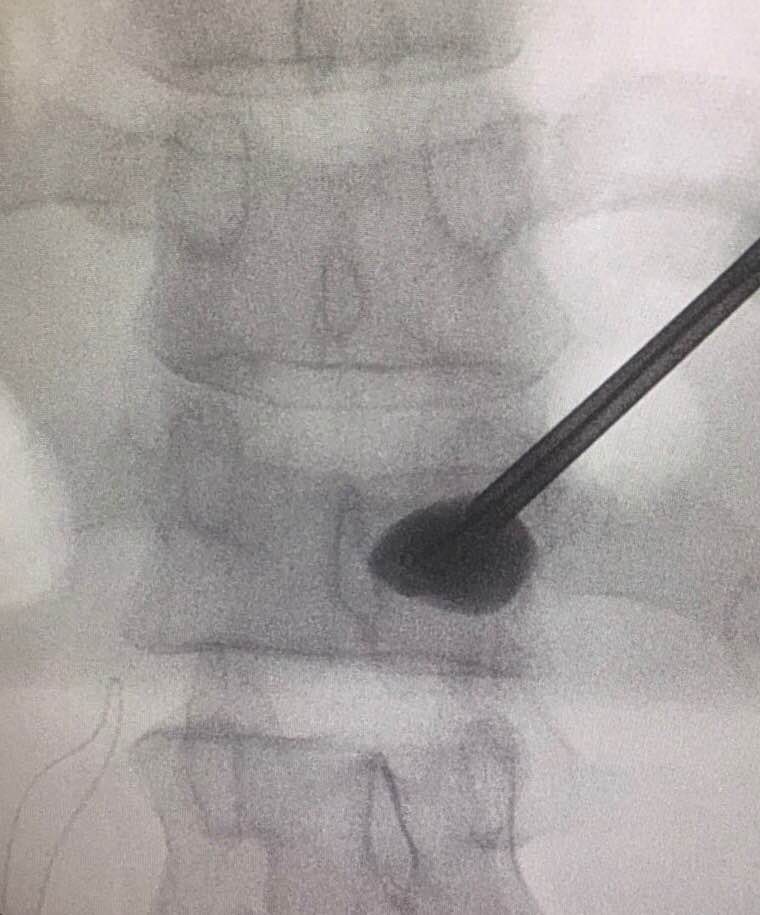

嚴重的工業意外受傷,T12胸脊椎不穩定的3段(前、中、後柱列)壓迫性脊柱椎體骨折

1. 即使您的胸部及胸脊椎柱被8英尺高和200磅重的巨大雪櫃嚴重壓碎, 您仍然生存, 您的中樞脊髓神經但沒有受到傷害.

2. 即使公立醫院忽畧了你不穩定的前、中、後3柱列的T12胸脊椎骨折,並在3天後容許你出院送回家, 你到私家醫院再進行第二次詳細檢查!

3. 幸運的是,入院前及兩天來你未有因為不穩定的脊柱椎體骨折碎片的移位而導致你脊髓中樞神經到不可逆轉和永久性的損傷致雙腿癱瘓及大小便失禁. 今天所有穩定你碎裂脊椎的手術都做完了.